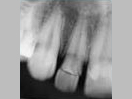

An unconventional way of treating Non-Vital Tooth with Apical Pathology with the help of MTA (Mineral Trioxide Aggregate)

MTA is placed in

the apical 5mm

of  Root Canal.

Rest part kept empty.

A Glass Fiber post is the process of being fixed within empty

part of Root Canal with the help of Composite Resin.

Tooth is prepared for receiving a crown.

X-ray after Preparation